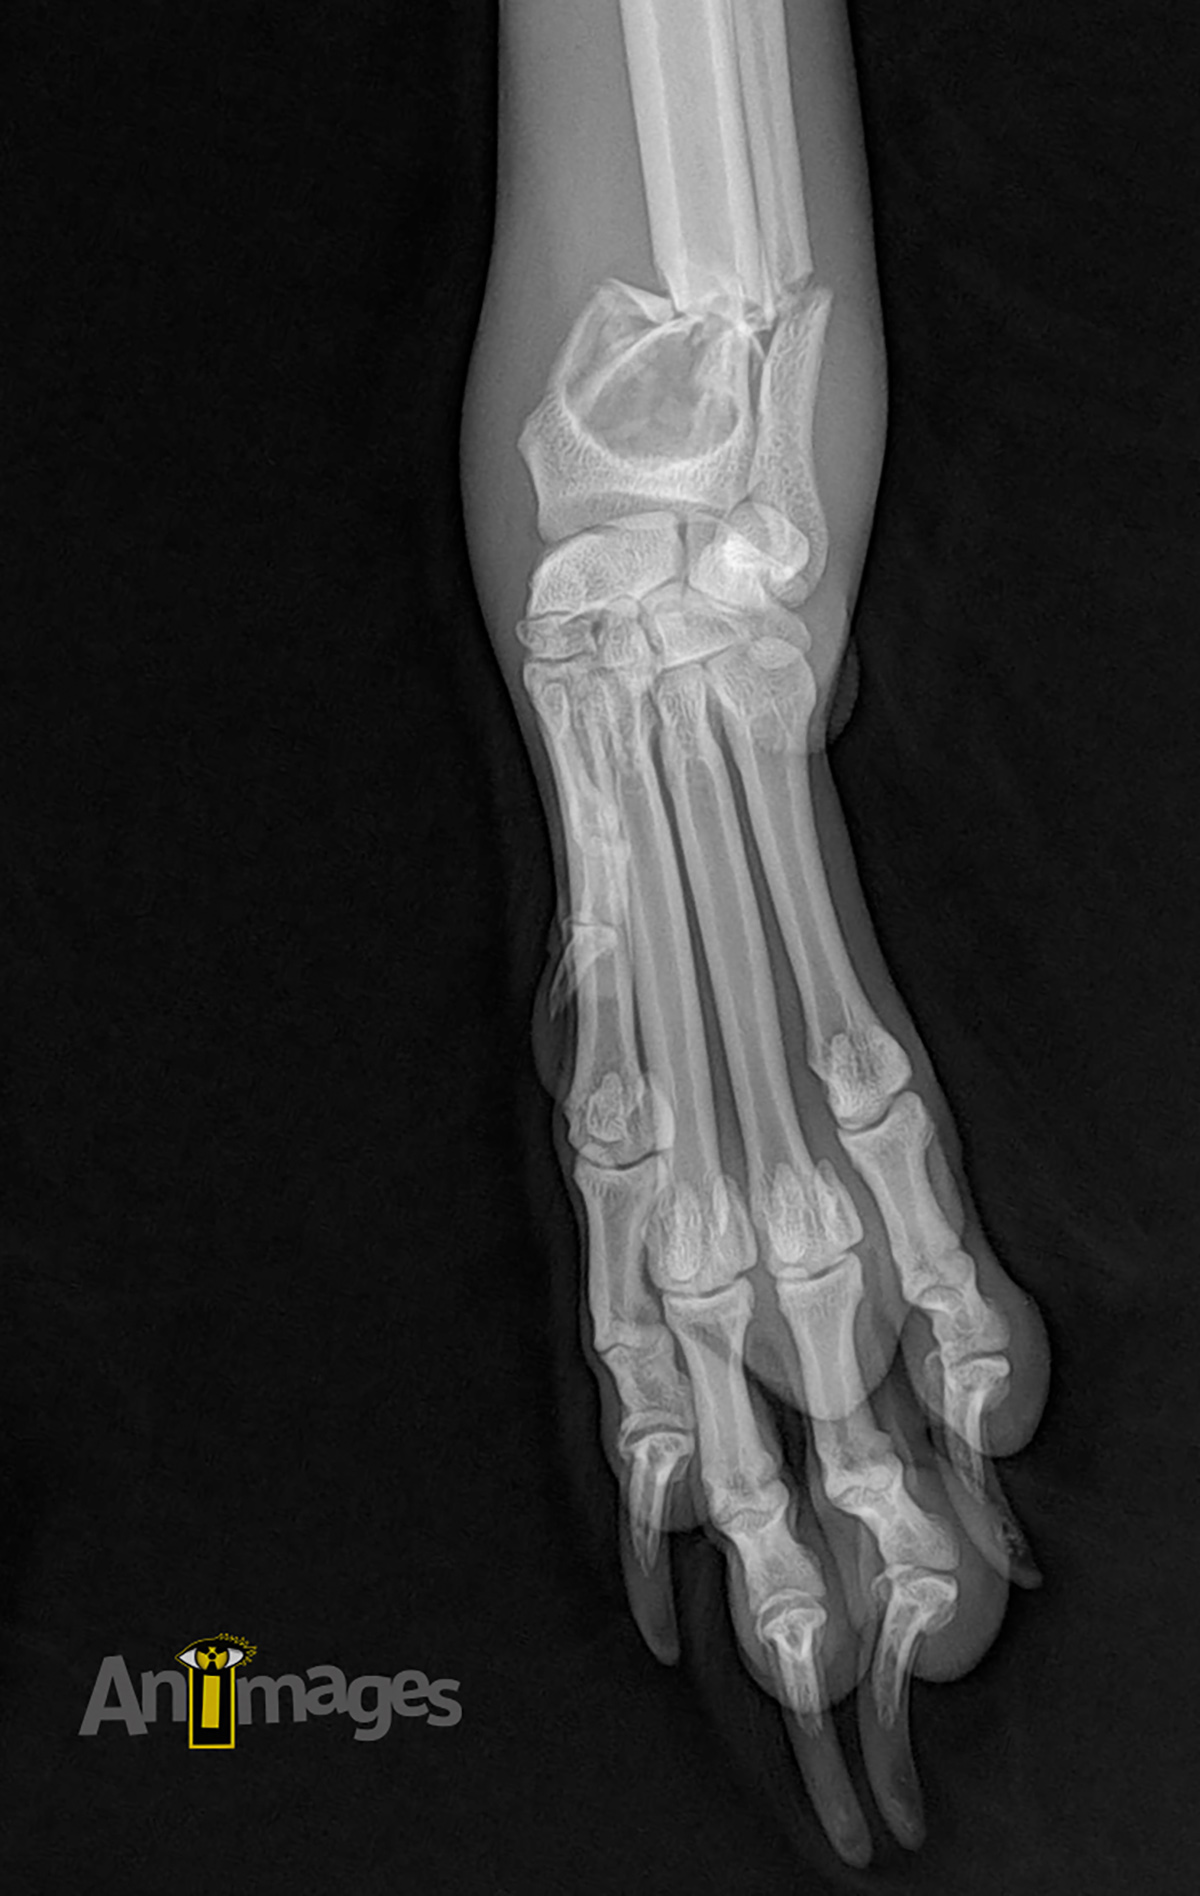

dorsopalmaire